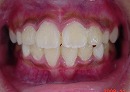

治療前の写真では、前歯が一本だけ咬み合わせが上下逆になっています。

治療後は、前歯の咬み合わせが改善しています。

期間は、1年6カ月で治療方法は独自の方法です。